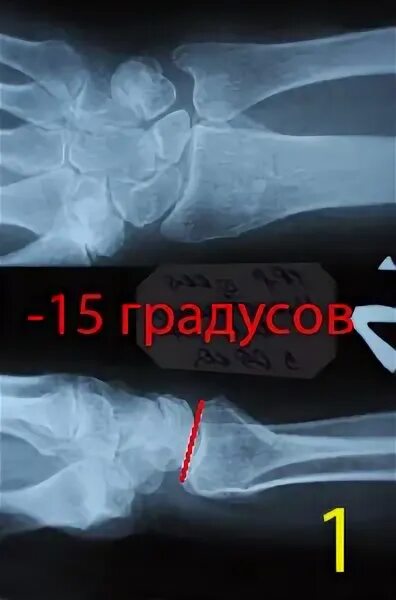

Чтобы быстрее сросся перелом руки